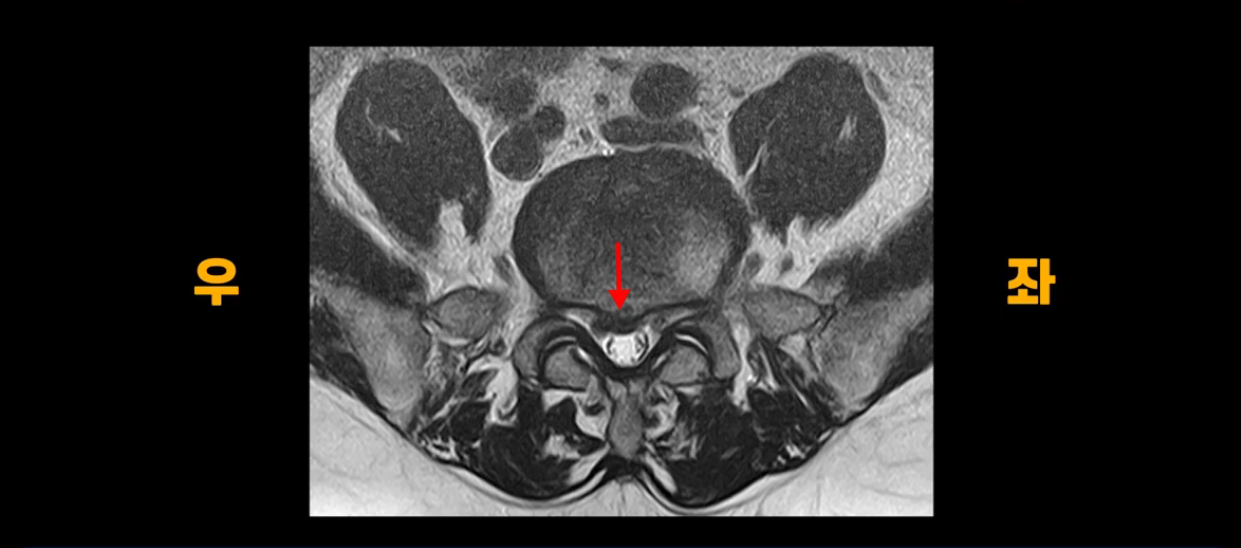

단면을 보면 중앙 오른쪽으로 밀려 나왔는데 파열이 아주 심하지는 않습니다.

아주 심한 상태가 아니라서 방사통만 있지 마비, 즉 힘 빠짐은 없는 상태입니다. 이 정도의 크게 심하지 않은 디스크 탈출 정도라면 신경 주사 맞고 버티다 보면 좋아질 수도 있지만, 이 환자분은 보존한 지 10개월 후에 증상이 더 나빠집니다. 왜 그럴까요? 신경 주사도 전혀 듣질 않는데 어떻게 해야 수술 없이 좋아질 수 있을까요? 지금부터 설명해 드립니다.